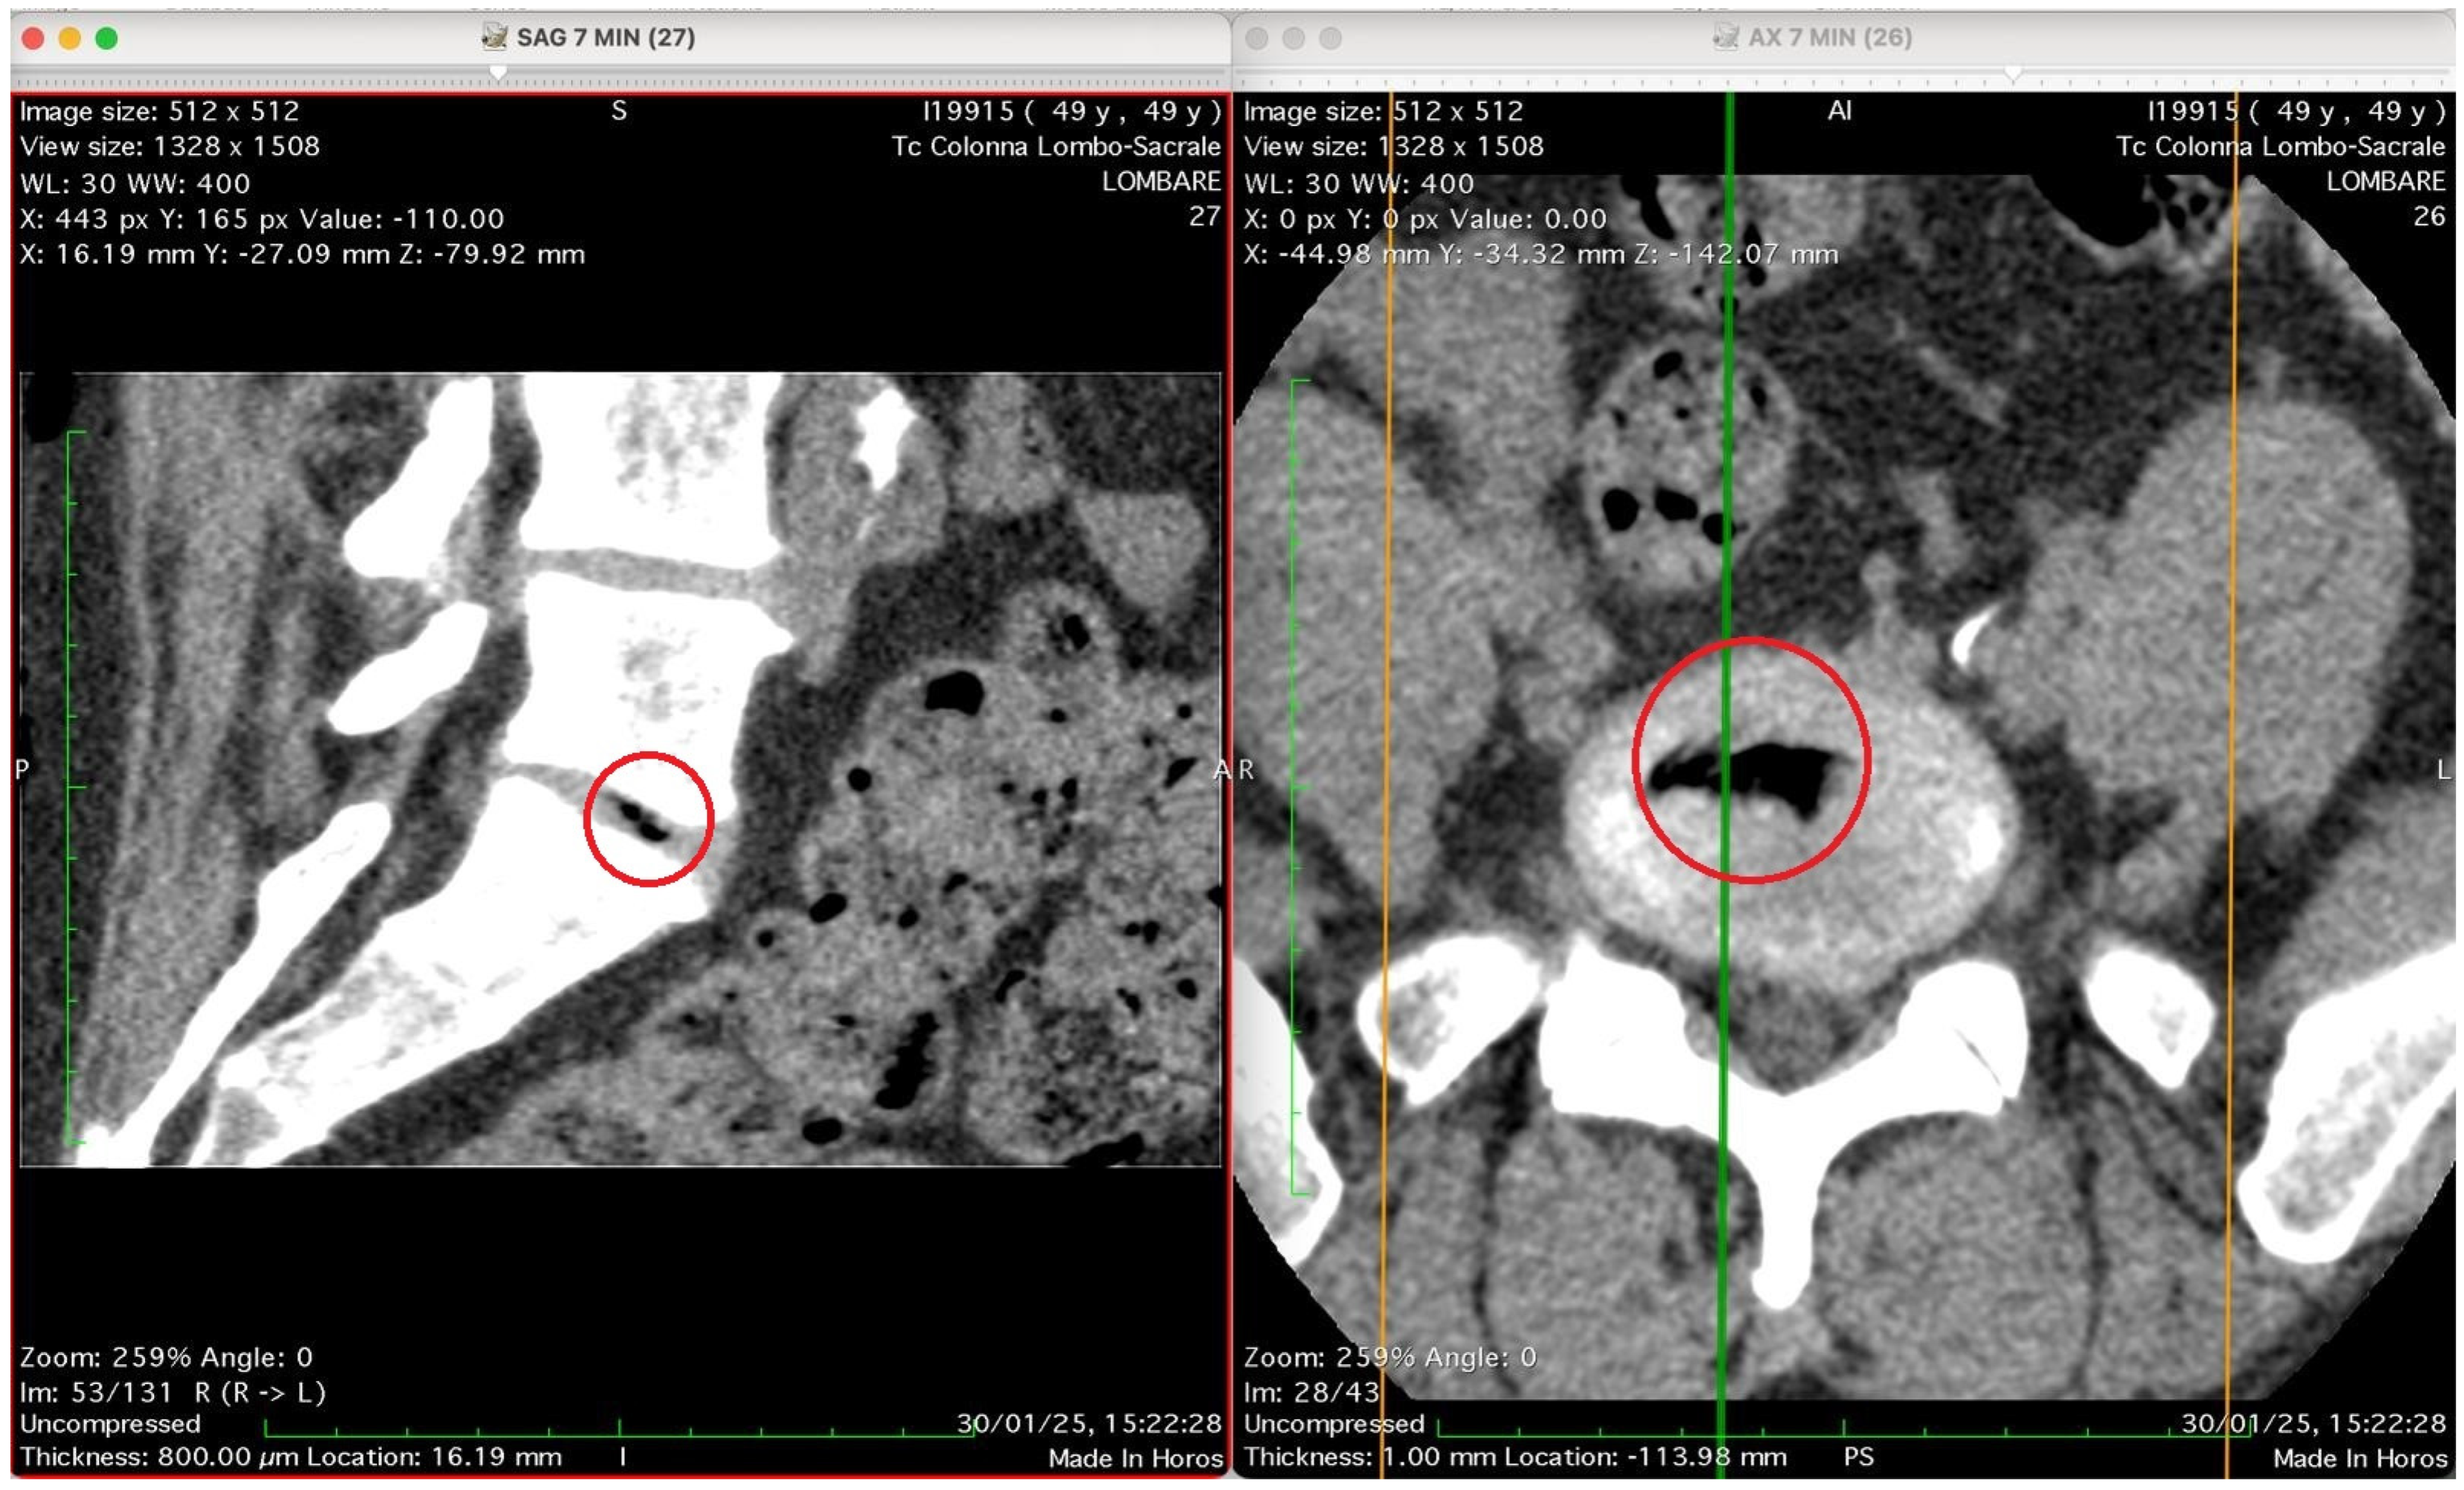

Figure 2, Figure 3, Figure 4 and Figure 5 show four computed tomography (CT) scans, along a time-course analysis, of the lumbosacral spine, visualized in sagittal (left) and axial (right) planes, from an exemplificative male patient (49 years) with L5-S1 herniated disc, undergoing an experimental setting of oxygen–ozone therapy via the intramuscular approach (Revolution™ CT, GE-Healthcare, Chicago, IL, USA). The very low-density ozone gas (hypodense, dark black within cred circles), spreads over the intervertebral disc within the time course of less than 10–20 min, assessing that ozone in the oxygen medium really reaches the morpho-functional area where the herniated disc is present in short times. A possible explanation is provided in the next paragraph.

At time 7 min is shown Figure 4.

This figure shows two CT images of the lumbosacral spine obtained in sagittal (left) and axial (right) planes from a CT lumbosacral study (Tc Colonna Lombo-Sacrale). Both images are co-registered (cross-referenced by coloured guide lines) and highlight the same anatomical level, marked with a red circle. Left panel (SAG 7 MIN, slice 27): This sagittal reconstruction depicts a clear intradiscal gas pocket at an intervertebral level (most probably L4–L5 or L5–S1). The gas appears as a sharply defined, elongated hypodense linear area (black) within the intervertebral disc space. The morphology suggests that the gas has collected along a fissure of the annulus fibrosus or within a cleft of the nucleus pulposus, typical of either a vacuum phenomenon from disc degeneration or gas migration following paravertebral intramuscular oxygen–ozone injection. The vertebral endplates and adjacent vertebral bodies appear intact, with no signs of osteolysis or fracture. Right panel (AX 7 MIN, slice 26): The axial CT slice confirms the presence of a gas inclusion in the centre of the discal space, delineated by the red circle. The gas pocket has very low attenuation (near air density) and a regular contour, lying entirely within the confines of the disc, without extension into the epidural space or paravertebral soft tissues. The vertebral canal is preserved, and no evidence of epidural or foraminal gas or mass effect on neural structures is seen. Technical data (from the annotations): Image matrix: 512 × 512 WL/W: 30/400 Slice thickness: 0.8 mm Acquisition time: 30 January 2025, 15:22:28. Interpretation summary: The paired sagittal and axial CT images demonstrate a well-defined intradiscal gas pocket consistent with intradiscal migration of gas, likely due to paravertebral oxygen–ozone diffusion through the annular fissures rather than direct intradiscal injection. The finding supports a mechanism of gas penetration via micro-fissures without needle breaching of the disc, a phenomenon occasionally observed after paravertebral oxygen–ozone therapy or in degenerative disc disease.